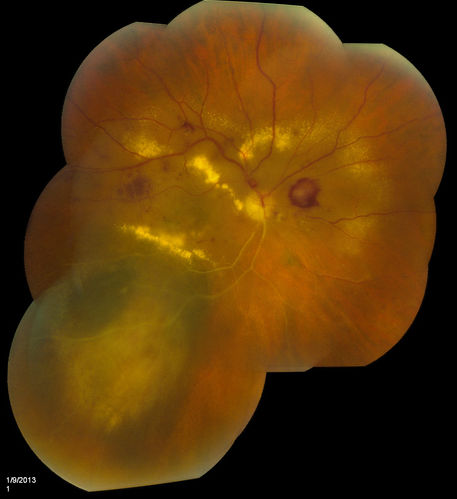

Choroidal Melanoma with Radiation Retinopathy

Patient comes with follow up on Choroidal Melanoma, Right Eye that was treated back in June of 2009 with Radioactive Implant. Vein Occlusion is also present with VA - Hand Motion. Hemorrhages visible with hard exudates from the Radiation Retinopathy.